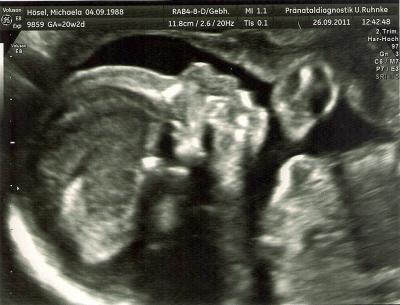

Hallöchen meine Damen! Nach einer fast schlaflosen Nacht (wor lauter Aufregung) hatte ich heute 12Uhr meinen Termin zur FD. Alles ist bestens und zeitgerecht entwickelt. Anfangs hat es ganz süß beide Hände vor´s gesicht gehalten und im Laufe der Zeit das süße gesicht gezeigt. Männe war mit und mind. genauso aufgeregt wie ich. Hat mir brav die hand gehalten mit kalt-schwitzigen Händen! Es ist 20cm groß und wiegt ca 262gramm. Bin sooooooo unendlich stolz.... Hier ein paar Daten: Kopfdurchmesser: 47,5mm Kopfumfang: 173,0mm Und den Rest muss ich erstmal googlen, was da was bedeutet! :) Und das beste kommt zum Schluß mit Bildchen im Anhang! *Trommelwirbel* * * * * * Es wird ein........ * * * * * JUNGE!!!!!!!!!!!!!!!!!!!!!! Ich freu mich so und der Papa freut sich auch riesig über den Stammhalter, obwohl ihm ein Mädel lieber gewesen wäre! Also reihe ich mich mal mit bei den Jungs-Mamas ein! Heute gibts das Bildchen von der FD und morgen folgt das nächste von der FÄ vom 2.Screening! Einen schönen sonnigen Wochenstart wünsche ich euch! Lieben Gruß, Michaela + Freund und Sohnemann inside =)

Bild zu Zurück von FD + OUTING!!!!!! - Forum für Februar - Mamis